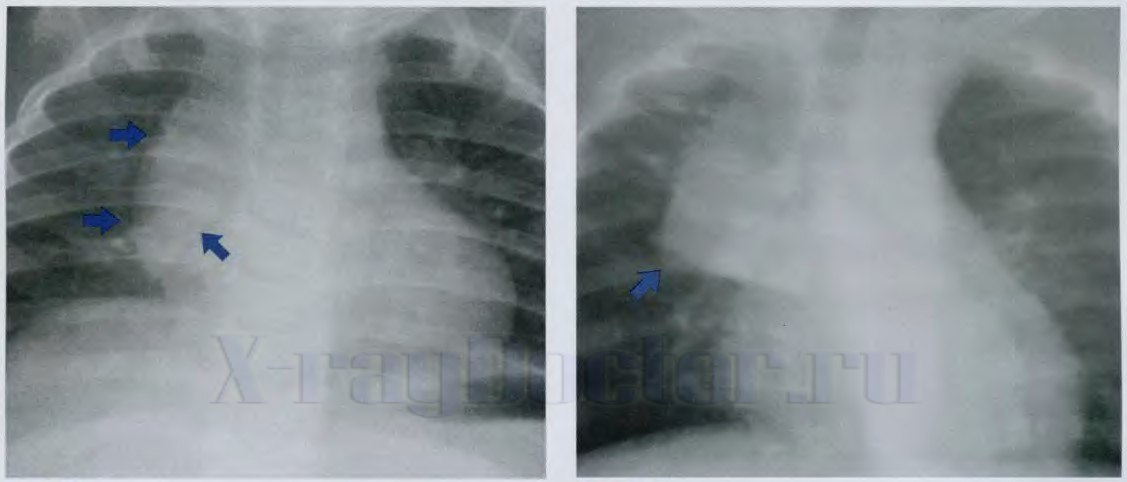

Какие рентгеновские признаки свидетельствует об увеличении тимуса:

- овальная или треугольная тень в верхнем средостении справа;

- лентовидное затемнение по обе стороны верхней части грудины.

Рентгенограмма позволяет изучить степени увеличения вилочковой железы:

- 1-я степень – затемнение не выходит на пределы внутренней трети грудной клетки;

- 2-я степень – тимус располагается в средней трети;

- 3-я степень – вилочковая железа прослеживается на снимке и не занимает более 2/3 легочного поля.

Определение увеличенной вилочковой железы у детей на рентгене легких осуществляется при экспозиции во время глубокого выдоха.